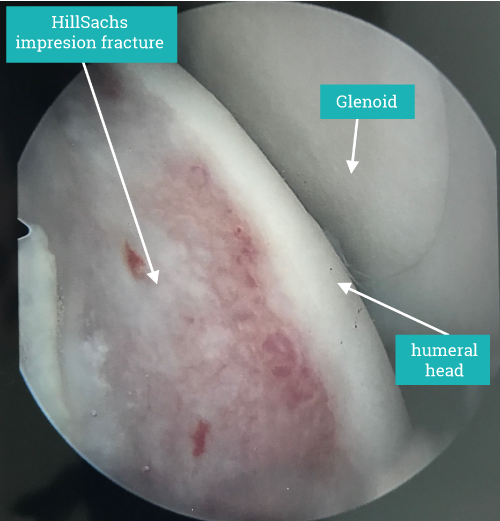

Hill Sachs Lesion

It describes the bone impaction caused by the humeral head sitting on the sharp angle at the front of the shoulder when it dislocates. Of itself it causes no long-term symptoms but can result in instability becoming persistent in the shoulder.

A symptomatic Hill-Sachs lesion is one that causes the shoulder to dislocate and surgery is based around preventing further dislocation either by addressing the primary cause at the front of the shoulder or in unusual cases addressing the Hill-Sachs lesion itself.